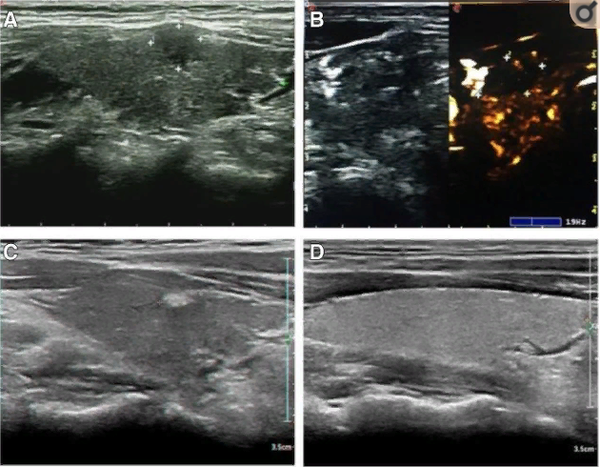

Эффективность метода наглядно демонстрируют снимки из исследования. На них видно, как узел размером около 8 мм (изображение А) был полностью разрушен. Через 6 месяцев после процедуры на его месте образовался небольшой рубец (С), который спустя полтора года практически полностью рассосался (D), не оставив следов в ткани здоровой железы.

Рисунок из указанной статьи. А — исходный узел. В — снимок с контрастом. С — состояние через 6 месяцев после абляции. D — результат через 1,5 года: рубец отсутствует.